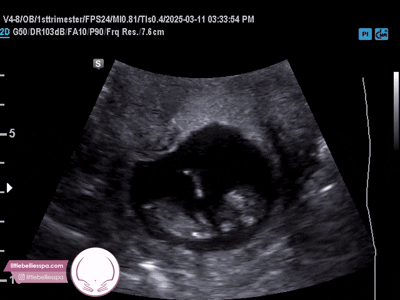

8 weeks

12 weeks

20 weeks

30 weeks